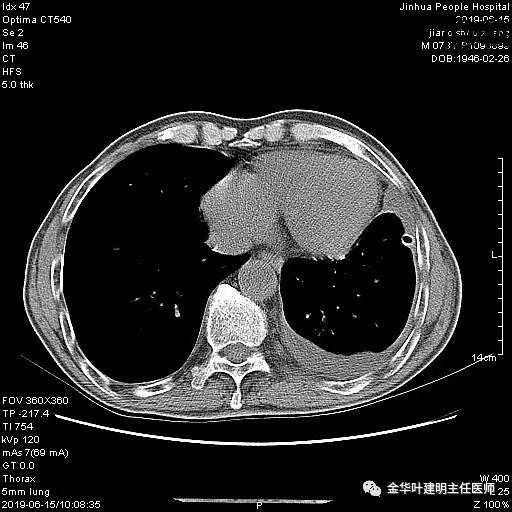

6.15上午:24小时胸管引流出血性液250ml;复查胸部CT示: